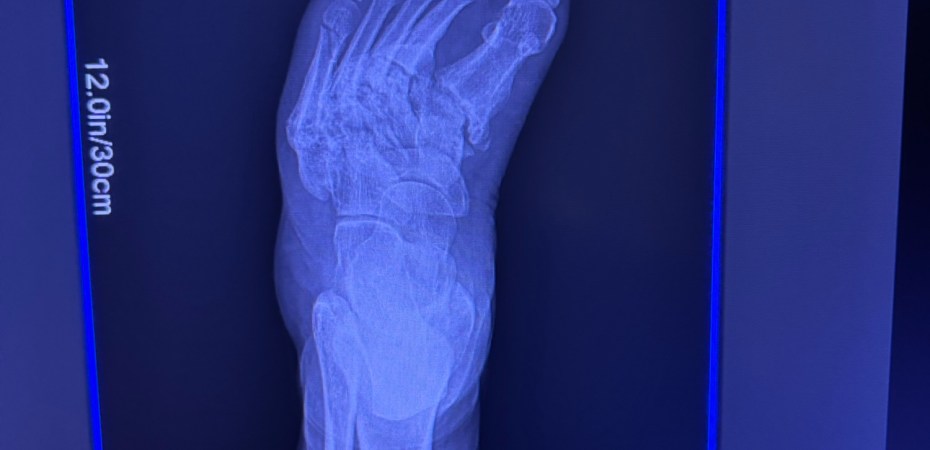

When I did get my X-rays, of course there is my perma-line of micro fractures across the top of my foot – *and* some apparent new ones. 🤦🏻♀️

(Also, the other views suggested some involvement with my ankle so ortho will need to take a look at that. 🤦🏻♀️)